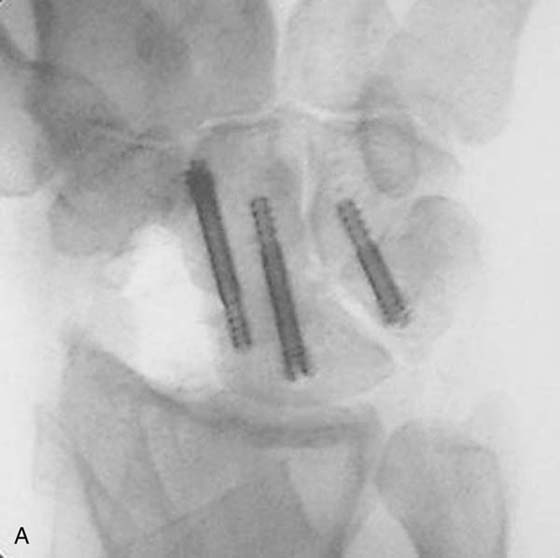

Four-Bone Arthrodesis

Watson and Ballet21 described the scapholunate advanced collapse (SLAC) deformity arising from chronic scapholunate instability. The scaphoid rotates, the capitate pushes in between the scaphoid and lunate, and degeneration occurs first at the scaphoid radial styloid joint (Fig. 76-4A) and then at the capitate lunate joint (see Fig. 76-4B). The radiolunate joint is spared and maintains good articular cartilage in most patients. Pain occurs from degenerative arthritis at the radial scaphoid and capitate lunate joints. For surgical treatment to succeed, this pathology must be addressed. The four-bone arthrodesis procedure removes the scaphoid to eliminate this focus of degeneration and fuses the lunate, capitate, hamate, and triquetrum to stabilize the wrist (Fig. 76-5B, online). This choice of intercarpal fusion prevents further capitate migration. It eliminates the midcarpal degeneration between the capitate and lunate and maintains carpal height. This fusion is also indicated in patients with radiocarpal arthritis from scaphoid nonunion and scaphoid AVN.

images

Figure 76-4 A, Scapholunate advanced collapse (SLAC) wrist. Note arthritis at scaphoid radial styloid joint. B, Severe SLAC wrist. Lunate radius joint is spared from arthritic involvement.

Figure 76-5 A, Four-bone fusion with scaphoid excision.